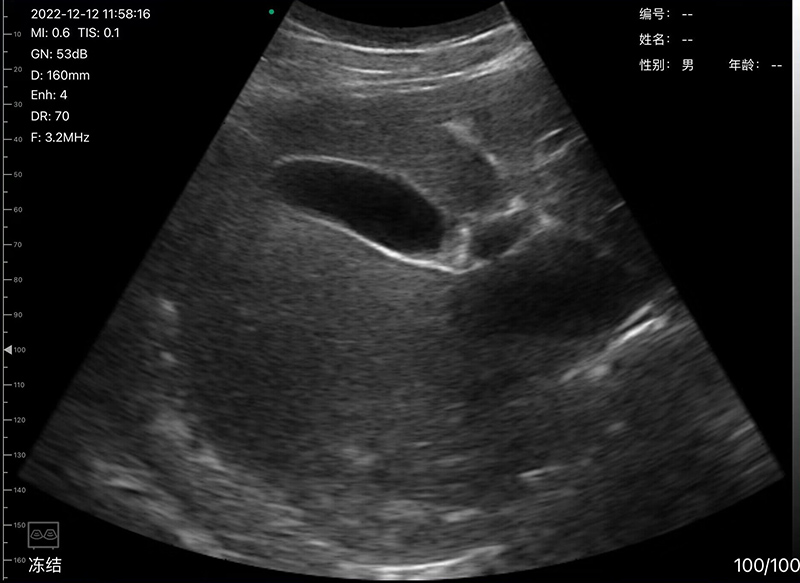

• Scan mode: Electronic Array Convex scanning

• Frequency: Convex probe 3.2/5.0MHz

• Scanning Depth: Convex 90-305mm, adjustable

• Display mode: B, B/M, Color, PDI, PW

• Playback : manual and automatic, playback frames to be 100/200/500/1000